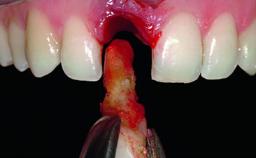

Replacement of an Ankylosed Upper Left Central Incisor: Bone Augmentation and Socket Grafting, Late Placement of an RC Bone Level Implant

| Bone Augmentation | Horizontal|Simultaneous|Staged |

| Augmentation Materials | Autogenous chips|Xenogenous |